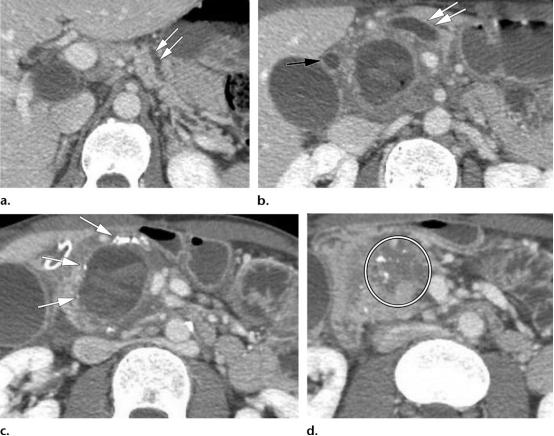

43岁男性,肿块形成型慢性胰腺炎,伴假性囊肿。

(a图,b图)轴位CT示主胰管弥漫增粗(两个平行排列的白色双箭头)以及扩张的胆总管(黑色长箭头),这也称为*管双**征。胰腺实质保存完好,胰管与胰腺实质的比值小于0.5。

(c图)轴位CT图示胰头区散在钙化灶(白色长箭头),在胰头区域可见囊性病变,伴血性内容物,符合假性囊肿表现。

(d图)轴位CT图示胰头区肿块样增大(白色圆圈)

49岁女性,胰腺导管腺癌与慢性胰腺炎。

(a图)轴位CT图示胰头边界不清密度稍低的肿物(白色圆圈),向外周推移的钙化(黄色长箭头),肠系膜上动脉(红色长箭头)与肠系膜上静脉(蓝色长箭头)比值为1,肠系膜上静脉呈泪滴征,血管周围脂肪间隙被肿物侵犯(白色长箭头)。

(b图)冠状位CT示扩张的胰管(白色五角星)及分支胰管(白色短箭头)。

(c图)轴位CT图示扩张的胆总管(两个平行排列的白色长箭头)。